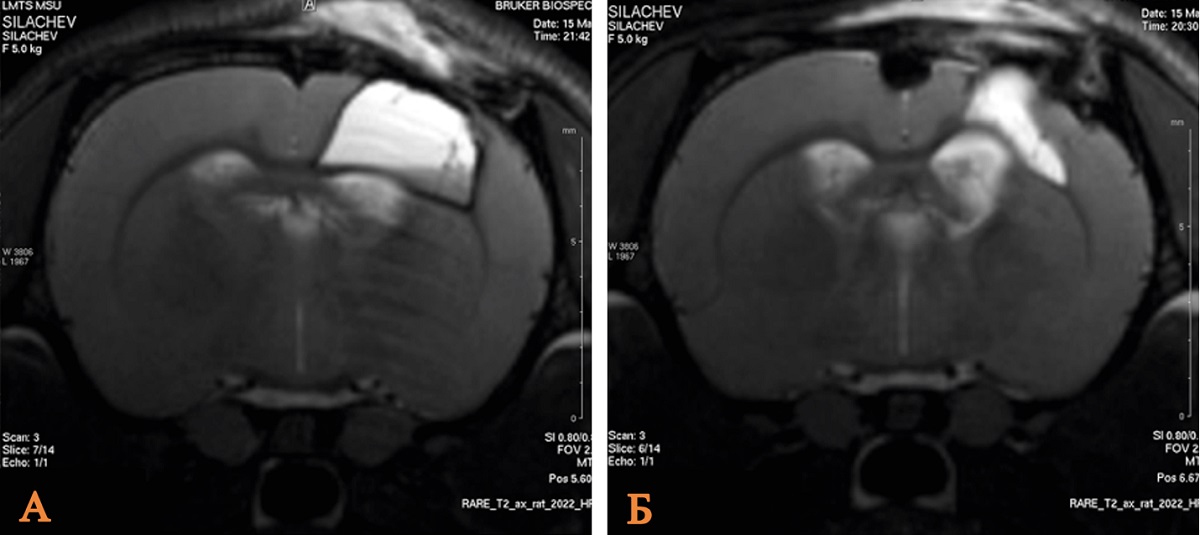

Сравнительный анализ томографических данных показал, что в группе, получавшей литий, объем повреждения головного мозга был достоверно ниже, чем в контрольной. Так, медианное значение данного показателя составило 20,5 мм 3 против 35,0 мм 3 в контроле, что подтверждает выраженный нейропротективный потенциал препарата при раннем отсроченном введении (рис. 1, табл. 1).

Рис. 1. МРТ зоны ушиба головного мозга крысы после введения хлорида лития в дозе 63 мг/кг через 60 мин в сравнении с контрольной группой

Примечание: А – группа Контроль; Б – группа ОЧМТ+Литий 60 мин/63 мг. Изображение авторов, получено в ходе оригинального исследования.

Таблица 1

Объем повреждения головного мозга крыс в группе ОЧМТ+Литий 60 мин/63 мг и группе сравнения по данным МРТ-изображений на 14-е сутки наблюдения

Группа | Объем повреждения головного мозга, мм 3 | p, значимость относительно ложнооперированных животных | p, значимость относительно контрольных животных |

Ложнооперированные животные (n = 10) | 12,0 [8,0–14,5] | – | – |

Контроль (n = 10) | 35,0 [30–36] | 0,0001 | – |

ОЧМТ+Литий 60 мин/63 мг (n = 10) | 20,5 [17–22,5] | – | 0,001 |

Примечание: составлено авторами.